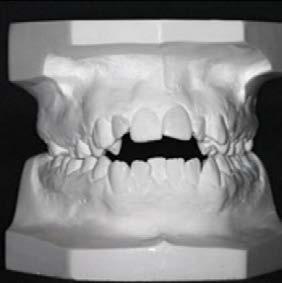

Figura 1. Fotografías intraorales: a) arcada superior, b) oclusión lateral derecho y c) oclusión central, d) oclusión lateral izquierdo y e) arcada inferior.

Al examen intraoral se observa arcada dental incompleta; con ausencia de órganos dentales 16 y 27 (Figura 1).